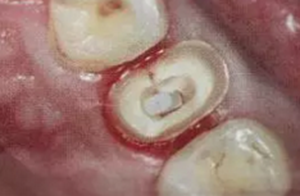

(根管內(nèi)殘留物)

個(gè)人見解:必要的情況下先開闊根管口建立一定的視角后,慢速手機(jī)上G鉆為引導(dǎo)鉆,由號(hào)遞增引導(dǎo)開闊通路;P鉆預(yù)備樁道,同樣需要由小向大號(hào)遞增,直到選擇好適合的號(hào)預(yù)備到規(guī)定測(cè)量的深度即可,再配合纖維樁系統(tǒng)中各型號(hào)纖維樁所匹配的樁道鉆,預(yù)備、修整成與纖維樁相適應(yīng)的樁道。

預(yù)備后根管壁上會(huì)不同程度的牙膠和封閉劑等殘留物,所以樁道預(yù)備前后建議X線片輔助檢查預(yù)備深度等情況,而殘留物也會(huì)很清晰地顯現(xiàn)。